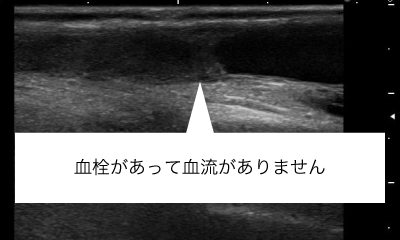

シャント血管が詰まってしまったとき(閉塞)などは、血栓を吸引するカテーテルをシャント血管内に挿入し、血栓を吸い取ります。

症例によりますが、シャント閉塞しても90%以上の患者さまは閉塞後7日間以内であればシャントを復活させることができます。